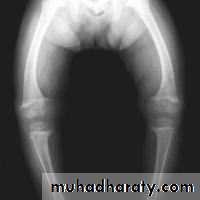

Genu varus (medial angulations)Genu valgus (lateral deviation)

Developmental knee deformities. Genu varus (bow leg). Genu valgus (knock knee);

During early years of life (before 10 years) these deformities can be regarded as normal stages of development & must be followed up frequently .

• Normal knee is at 5-7 degrees of valgus, anything less is genu varus, anything more is genu valgus and any abnormal hyperextension is genu recurvatum.• Causes can be developmental, congenital or secondary acquired.